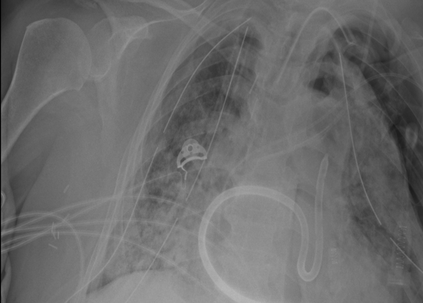

Tuberculosis remains a critical global health issue, particularly in resource-limited and remote areas. Early detection is vital for treatment, yet the lack of skilled radiologists underscores the need for artificial intelligence (AI)-driven screening tools. Developing reliable AI models is challenging due to the necessity for large, high-quality datasets, which are costly to obtain. To tackle this, we propose a teacher--student framework which enhances both disease and symptom detection on chest X-rays by integrating two supervised heads and a self-supervised head. Our model achieves an accuracy of 98.85% for distinguishing between COVID-19, tuberculosis, and normal cases, and a macro-F1 score of 90.09% for multilabel symptom detection, significantly outperforming baselines. The explainability assessments also show the model bases its predictions on relevant anatomical features, demonstrating promise for deployment in clinical screening and triage settings.